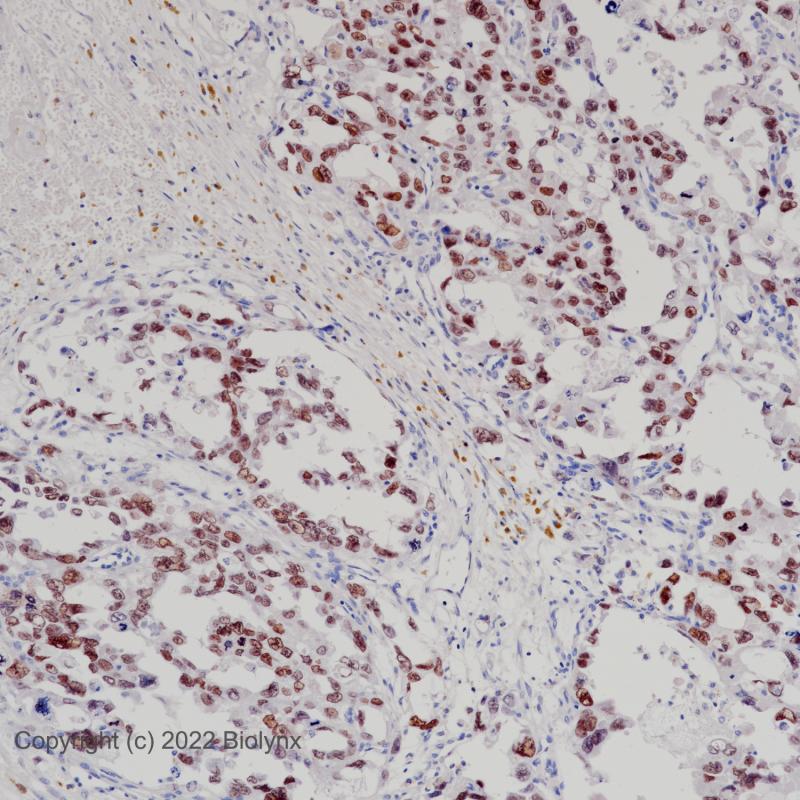

AR-V7 重组兔单克隆抗体

AR V7属于核激素受体家族。它含有核受体DNA结合域。类固醇激素受体是配体激活的转录因子,调节真核基因的表达,影响细胞增殖和分化的目标组织。转录因子的活性受结合共激活因子和共抑制因子的调节。该靶点是雄激素受体的剪接变体,缺乏c端雄激素结合位点。AR-V7在前列腺癌的发生、发展和耐药性的产生中具有重要意义。

阳性对照

前列腺癌

亚细胞定位

细胞核